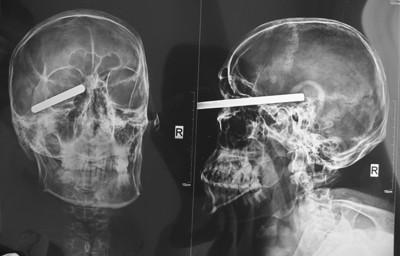

10多厘米长、铅笔粗钢柱从男子眼下扎进大脑。经过4个小时的手术,钢柱被取了出来。记者 朴峰 摄

射钉器里喷出的一根钢柱没有按预定钉入墙体,却径直飞向工人面部,10多厘米长、铅笔粗的钢柱顺着眼眶下方直入他的大脑。

在医院,医生很快为其实施了详细检查,经过影像学检查,医生发现钢柱扎进体内部分大约也有5厘米,已经扎进了于立的脑组织里了。眼球、大脑,这些器官哪一个对于于立而言都至关重要,如果得不到及时治疗,后果不堪设想,所幸此时于立的意识依旧清醒。

医生明确抢救方向,必须及时将异物取出并清创。次日凌晨1时许,医生经过充分准备后,决定为其实施手术将钢柱取出。手术由神经外科主任医师吴文霄主刀,由于伤口紧挨眼部,眼科医生刘妍也参与其中。手术持续了大约4个小时,医生终于成功将钢柱从于立的体内取出。手术结束后,医生又采取一系列措施防止其颅内感染和脑水肿。